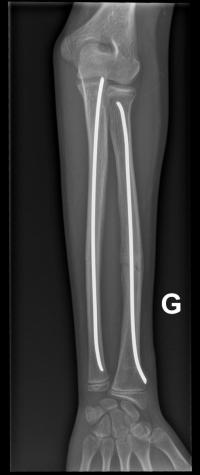

Fracture de l’avant-bras 31 mars 202519 mars 2024 par Damien Traitement Traitement orthopédique Embrochage centro-médullaire